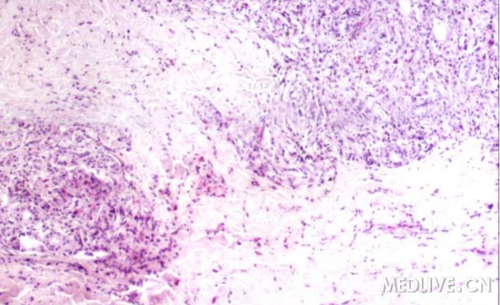

上肢着色芽生菌病